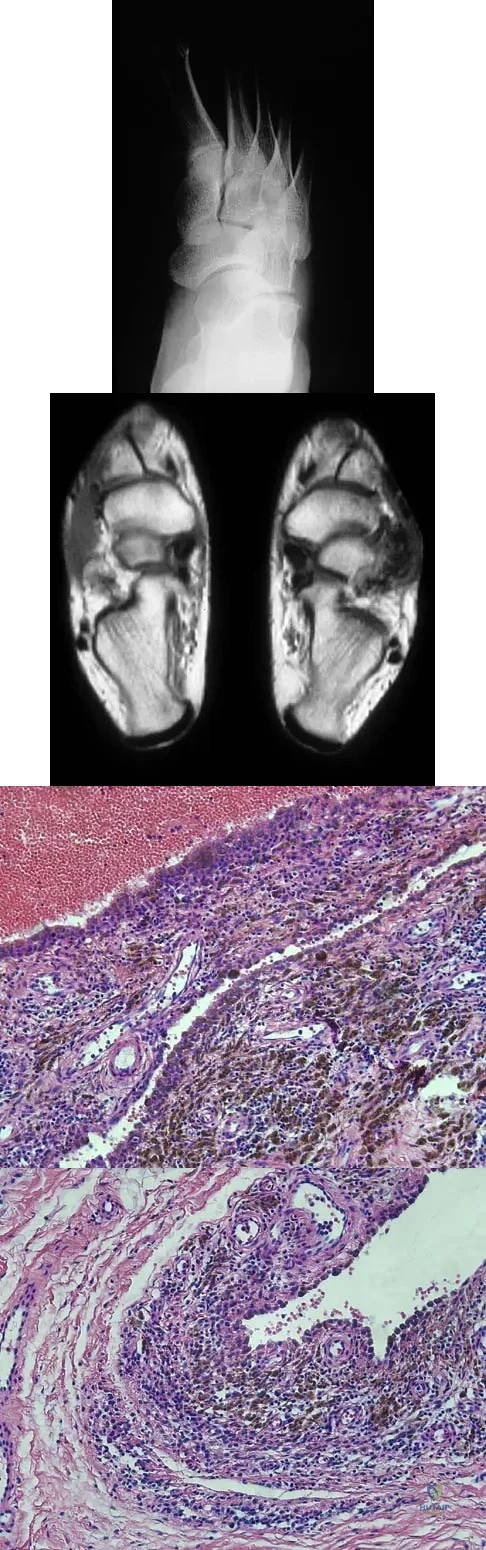

A 16-year-old girl has a painful foot mass. A radiograph, MRI scan, and biopsy specimens are shown in Figures 35a through 35d. What is the most likely diagnosis?

Synovial sarcoma should always be considered in the differential diagnosis of a foot mass; however, the histopathology shows a typical example of PVNS, with hemosiderin, giant cells, and synovium. Synovial chondromatosis would have metaplastic cartilage in the synovium. The radiograph shows subtle erosion of the lateral cortex of the cuboid, and the MRI scan shows a soft-tissue mass. Ghert MA, Scully SP, Harrelson JM: Pigmented villonodular synovitis of the foot and ankle: A review of six cases. Foot Ankle Int 1999;20:326-330. Jones BC, Sundaram M, Kransdorf MJ: Synovial sarcoma: MR imaging findings in 34 patients. Am J Roentgenol 1993;161:827-830. Sartoris DJ, Resnick D: Magnetic resonance imaging of pediatric foot and ankle disorders. J Foot Surg 1990;29:489-494.